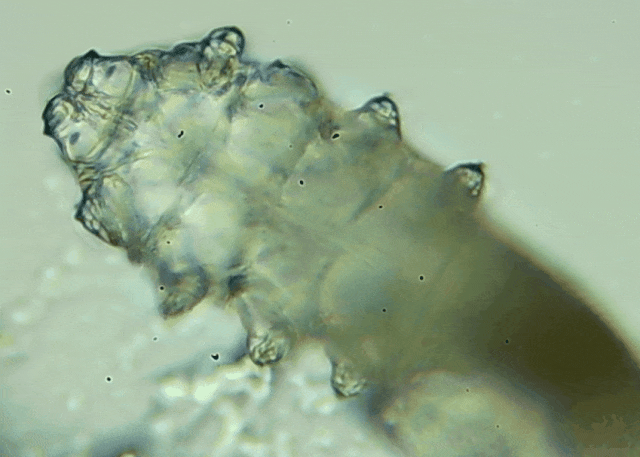

我只是眼睛癢,結(jié)果醫(yī)生說我睫毛里有80只蟲?這不是恐怖片,而是真實的病例:武漢一13歲男孩,右眼9根睫毛里檢出39只螨...[詳細(xì)]